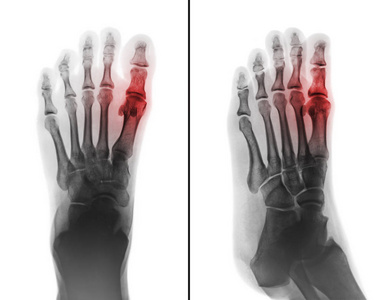

第一跖趾关节疼痛是急性痛风的典型表现。 56%78% 的痛风患者的初始表现为第一跖趾关节疼痛。 当患者出现第一跖趾关节疼痛时,医生会首先考虑为痛风发作。 但是导致第一跖趾关节疼痛的原因却并非只有痛风,虽然有 57% 的患者被确诊为痛风,但是仍有有 临床表现为趾过度向外偏斜,超过了生理性外翻角度(即外翻角>15°),伴跖趾关节内侧隆起 (见图1)。 该病女性多见,发病率男女比例约115。 外翻是如何"炼"成的请输入验证码以便正常访问 您的IP是:2149 如果经常出现此页面,请把您的IP和反馈意见 提交 给我们,我们会尽快处理,非常感谢。 为什么会出现验证码? 出现验证码表示您所在的网络可能存在异常,同IP短时间内大量发送请求,被服务器判断为异常IP

痛风 风湿性关节炎 影片x 射线脚和关节炎在第一跖趾关节 医学和科学backg 库存图片 图片包括有背包 痛苦